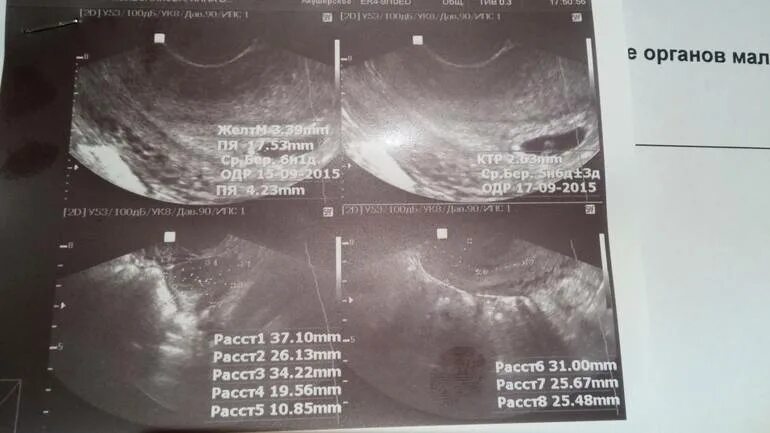

На каком сроке увидели плодное яйцо